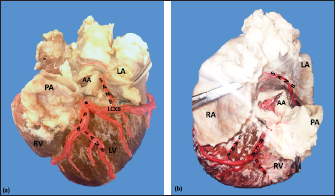

The LCA caliber and length were 9.4 ± 1.2 and 18.3 ± 4.8 mm, respectively. This artery was divided into two branches (PIB and LCXB) in 24 (85.7%) of the cases and trifurcated into PIB, LCXB, and left diagonal branch (LDB) in four (14.3%) specimens (Fig. 3). The LDB presented a caliber of 3.4 ± 0.8 mm, a length of 106.8 ± 40.3 mm, and ended in the same percentage in the upper and lower third and ended in the same percentage in the upper and lower third of the obtuse face of the heart (Table 1) (Fig. 3).

The PIB ended in 13 (46.4%) cases in the apex, followed by 42.9% in the posterior aspect of the left ventricle and to a lesser extent in the lower third of the paraconal interventricular sulcus (10.7%). The PIB presented five right branches on average and six left branches. The proximal caliber of this main arterial branch was 6.4 ± 1.4 mm, the intermediate caliber was 4.6 ± 1.1 mm, and the distal caliber was 2.9 ± 0.7 mm. Its length was 202 ± 25.2 mm (Fig. 3).

The LCXB ended in 23 specimens (82.1%) in the subsinusal interventricular sulcus and in 17.9% in the posterior aspect of the right ventricle. Its length was 149.1 ± 12.6 mm, and the calibers were as follows: proximal caliber was 5.9 ± 1.2 mm, the intermediate was 4.8 ± 0.9 mm, and the distal was 3.8 ± 0.9 mm. (Fig. 3).

The proximal calibers of the PIB and the LCXB did not present statistically significant differences (p=0.137). The length between the PIB and the LCXB presented statistically significant differences (p < 0.001), being greater in the PIB and covering more territory of the left ventricle.

Fig. 3. Left surface of the heart. Division into two branches of the LCA (*) (a); division into three branches of the LCA (b). (LA): Left atrium; (LV): Left ventricle; (RV): Right ventricle; (PA): Pulmonary artery; (PIB): Paraconal interventricular branch; (LCXB): Left circumflex branch; (LDB): Left diagonal branch; (LCB): Left cone branch; (**): Left marginal branch; (LAVB): First left anterior ventricular branch; (#):MB.

The LCB, a branch of the PIB, presented a caliber of 1.8 ± 0.5 mm and a distance to the origin of the coronary ostium of 16.9 ± 8.2 mm (Fig. 3). The first left anterior ventricular branch (LAVB) of the PIB had a proximal caliber of 3.6 ± 1.1 mm and a distal caliber of 2.1 ± 0.8 mm. Its length was 118.5 ± 43.4 mm and the distance to the origin of the PIB was 19 ± 7.7 mm. It ended in the lower third of the left ventricular wall in 11 (39.3%) cases (Table 1) (Fig. 3). The left marginal branch (LMB), a branch of the LCXB, had a proximal caliber of 2.9 ± 0.7 mm, a distal caliber of 1.9 ± 0.6 mm, and a length of 79.1 ± 26.2 mm. Its ending was observed in the middle third of the obtuse face of the heart (57.1%) (Table 1). The proximal caliber of the LMB was greater among the branches that ended in the middle third compared with those in the upper third (p=0.003). This branch presented a distance to the apex of 76.4 ± 30.3 mm (Fig. 5).